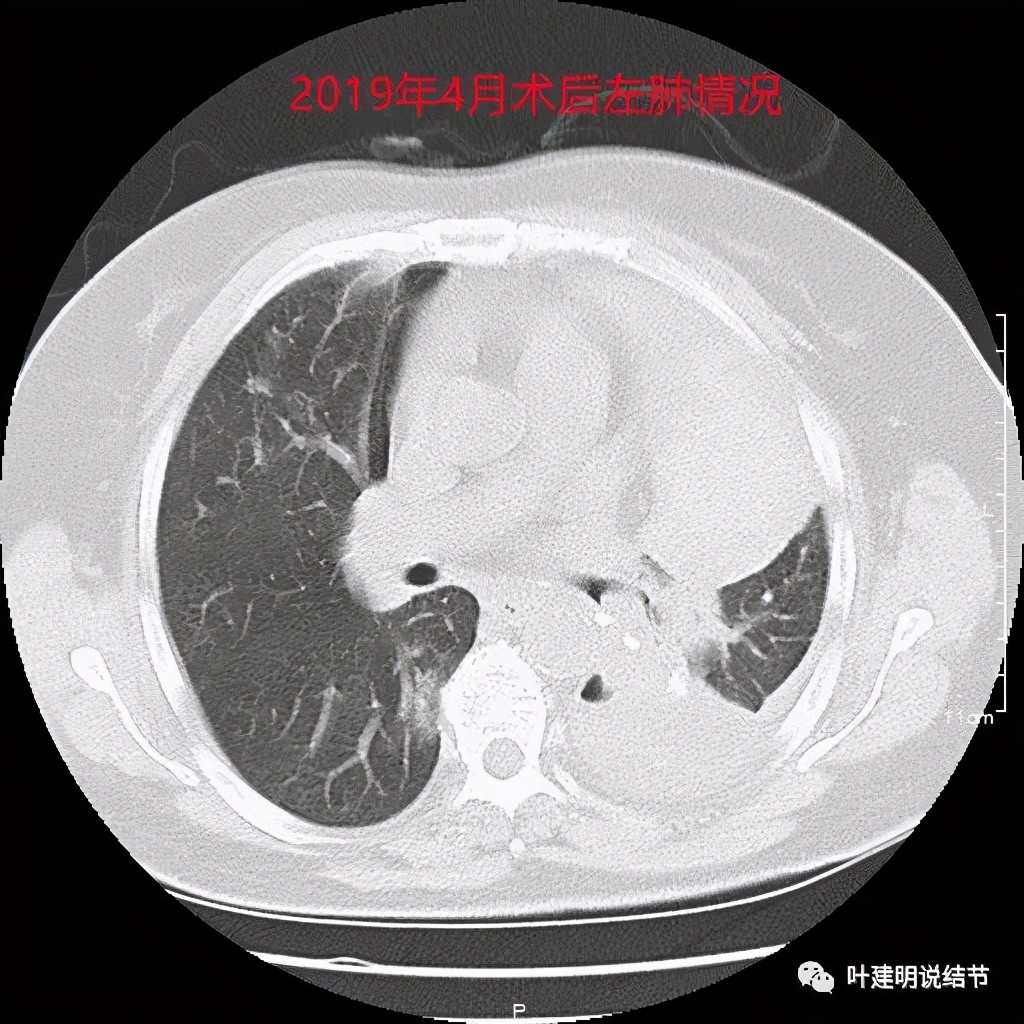

上图是当时的病理报告。上叶是支气管囊肿伴上皮鳞状化生,伴囊内真菌感染;左下叶是浸润性腺癌,乳头型为主,部分腺泡型,淋巴结是阴性的。但她的肺确实是影响大,下面是术后左肺的样子:

就留这么点肺,还是膨胀开了,虽然恢复慢,最后终于逐渐好转了一些: